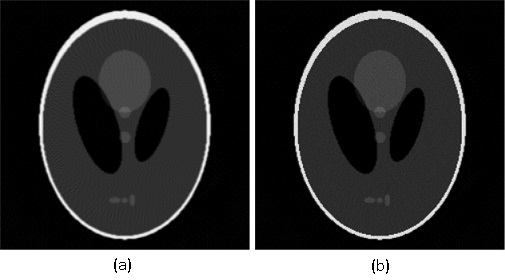

Given the problems we have pointed out regarding the first randomized algorithm, we have focused on the results obtained by the second randomized algorithm. For the parameters that we have fixed above, the results obtained by running the second randomized algorithm with 125000 iterations are given in Fig. 4 and Fig. 5 (Fig. 4 (a) is Fig. 2, and Fig. 5 (a) is Fig. 3). In both cases, the correction is significant, and the result of correction is very close in terms of reconstruction quality to the result obtained by running each of the two analytical algorithms alone with full view of 360 projection angles. That is, the result shown in Fig. 4 (b) is comparable to the result shown in Fig. 6, and the result shown in Fig. 5 (b) is comparable to the result shown in Fig. 7, which means a reduction in the number of views of (in Figs. 6 and 7 the reconstruction is more homogeneous, but with more visible artifacts). From the experiments we have conducted, we have remarked that the number of views can be reduced up to about and the results are still comparable to the results obtained by the analytical algorithms with full view, provided an appropriate number of iterations is chosen.